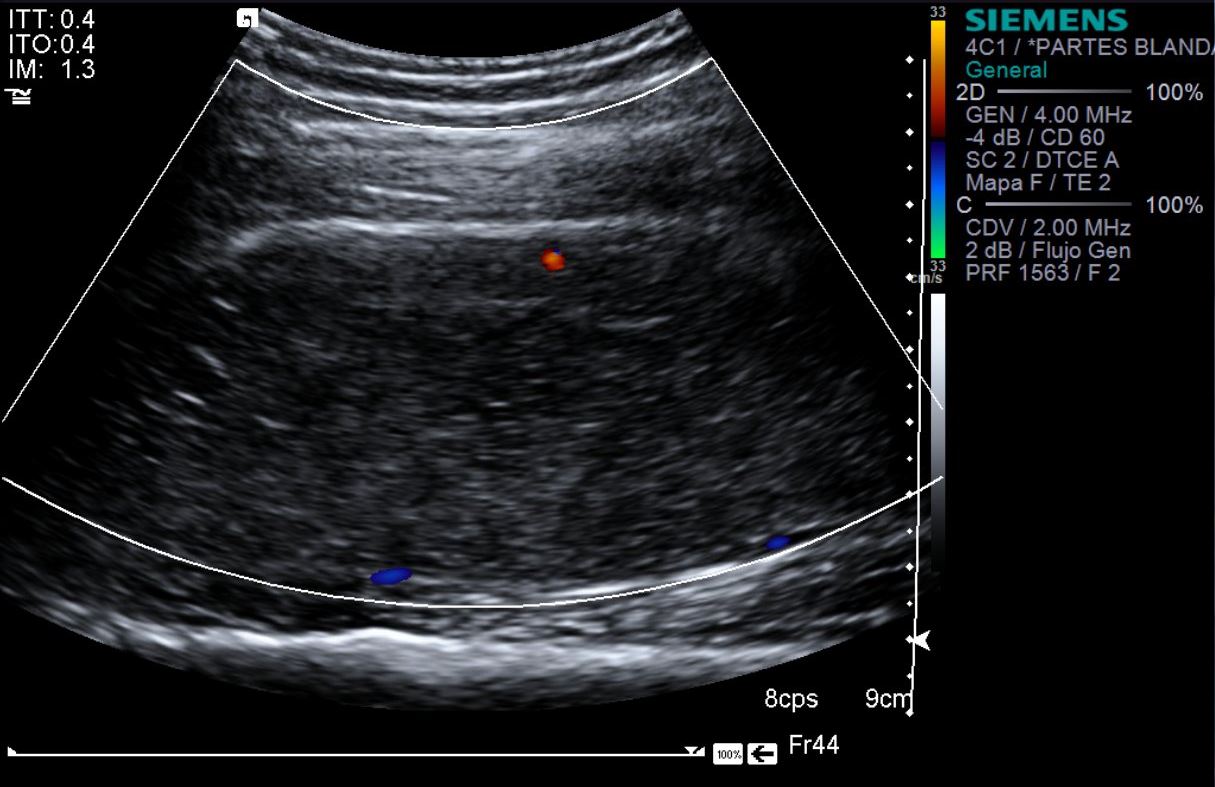

eco modo b

eco doppler